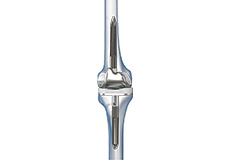

Total Knee Replacement

Total knee replacement, also called total knee arthroplasty, is a surgical procedure in which the worn out or damaged surfaces of the knee joint is removed and replaced with an artificial prosthesis.

Knee Implants

Knee implants are artificial devices that form the essential parts of the knee during a knee replacement surgery. The knee implants vary by size, shape, and material. Implants are made of biocompatible materials that are accepted by the body without producing any rejection response. Implants can be made of metal alloys, ceramic or plastic, and can be joined to the bone.